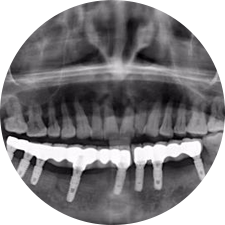

口腔種植是將人工牙根通過手術(shù)植入牙骨內(nèi),獲得牙槽骨牢固的支持,通過特殊的裝置和方式連接牙修復(fù)體,獲得與天然牙功能、結(jié)構(gòu)以及美觀相似的效果。

河北惟德口腔醫(yī)院擁有國內(nèi)豐富的半口/全口、即刻負(fù)重種植案例,十八年案例跟蹤分析,總結(jié)梳理出的各種不同類型的種植案例,Nobel種植體系針對半口/全口缺牙患者,通過4-8顆種植體可快速達(dá)到牙齒重建,不僅植入種植體較少,節(jié)省費用,手術(shù)時間更短。

術(shù)前患者CBCT口掃1:1三維重建,模擬手術(shù)過程及預(yù)測術(shù)后治療效果,確定每顆植體植入的適合的種植位點、深度及角度,有效避免損傷頜骨重要解剖結(jié)構(gòu),提高手術(shù)準(zhǔn)確度與安全性。

Noble口腔種植體系基本不受年齡限制,適用于缺牙修復(fù),也適用于牙槽骨萎縮、骨質(zhì)疏松、高血壓、糖尿病、超高齡的患者,即種即用,只需少量微小種植體,便可輕松微痛快速重建全口咬合,特殊力學(xué)設(shè)計,針對許多年紀(jì)較大,骨質(zhì)條件差,身體耐受力差的缺牙老人也能完成“即種即用”,受到廣泛好評。

惟德口腔種植體系是以患者感受為中心,取代傳統(tǒng)種植牙手術(shù)需要翻瓣、打孔、縫合,術(shù)前、術(shù)中、術(shù)后的繁復(fù)流程,采用3D導(dǎo)航微創(chuàng)準(zhǔn)確種植技術(shù),通過數(shù)字化CAD/CAM掃描技術(shù)獲得缺牙患者口腔數(shù)據(jù),以數(shù)據(jù)為基礎(chǔ)重建口腔模型進(jìn)行模擬種植。

術(shù)前將患者口內(nèi)的CBCT數(shù)據(jù)及咬合關(guān)系上傳到計算機(jī)中,建立1:1三維重建,模擬手術(shù)過程及預(yù)測術(shù)后治療效果,找出較佳種植位點、深度及角度,獲取實際種植體在頜骨內(nèi)的具體三維位置,有效避免損傷頜骨重要解剖結(jié)構(gòu),大大降低手術(shù)風(fēng)險,提升種植成功率。